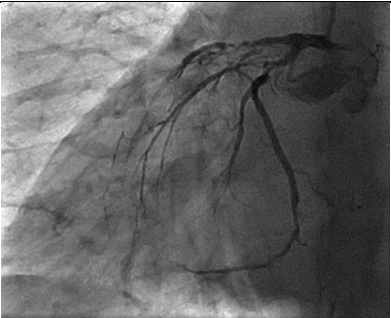

The patient then underwent elective coronary angiography which showed a Normal Left Main,  100% occluded Left Anterior Descending Artery, filling from right sided collaterals, a proximal 80% in the left circumflex with a 99% occluded OM1. The RCA had a proximal 80% lesion with a diffusely diseased acute marginal branch.

Figure 2 LAO Caudal View showing disease in the proximal LCX as wel disease in the proximal OM